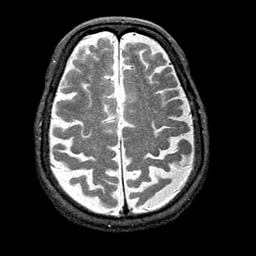

Alzheimer's disease MR T2-weighted -- Slice #35

[Home][Help][Clinical][Tour 1][Tour 2] Slice 35